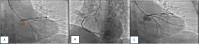

Fig. 2

Early PCI procedure. a A diagnostic angiography revealed diffuse stenosis 70–80% at proximal LAD, diffuse stenosis 80–90% at proximal LCx, and total occlusion at proximal OM1 with TIMI Flow 0 (red arrow). b Right coronary artery (RCA) was dominant with discrete stenosis of 30–40% at osteal. c Successful PCI with implantation of 2.25 × 22 mm coronary stent at proximal OM1 with TIMI Flow 3